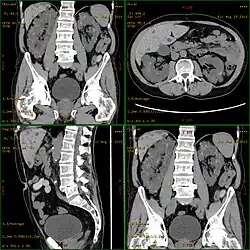

| Severely affected polycystic kidneys removed at the time of transplantation | |

| Diagnostic method | MRI, CT scan, Ultrasound[1] |

Polycystic kidney disease can be ascertained via a CT scan of abdomen, as well as an MRI and ultrasound of the same area.[23] A physical exam/test can reveal enlarged liver, heart murmurs and elevated blood pressure.[1]